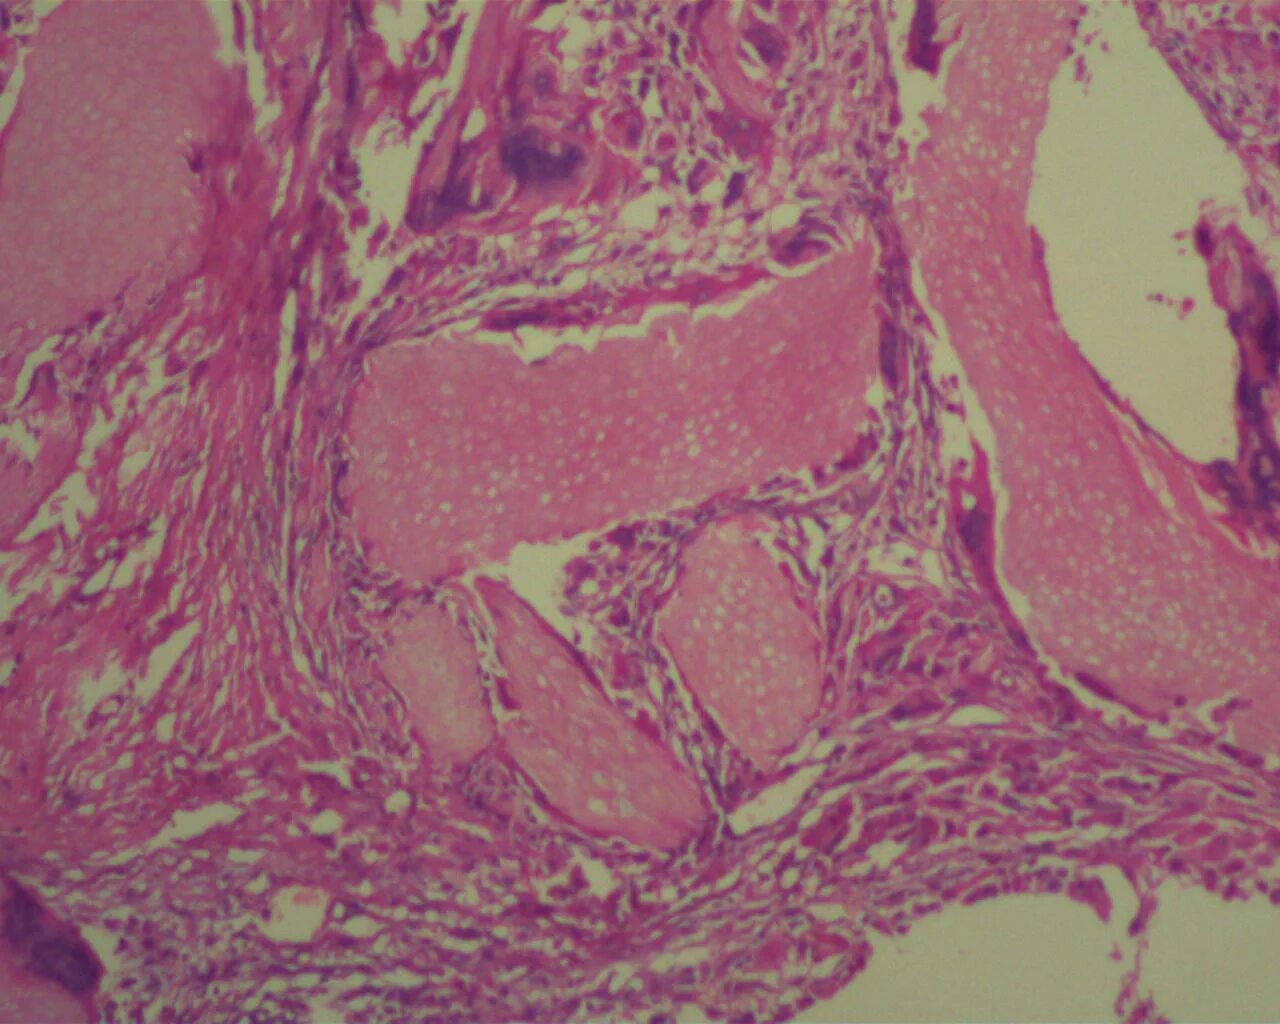

Ошибочная гистология